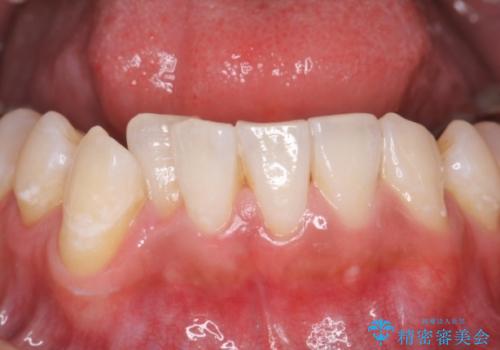

- 結婚式を控えており、それまでに歯を白くしたいということで来院されました。

歯医者に来院するのが久しぶりの様で歯の表面に汚れが付着しているとホワイトニング薬剤の効果が薄れるため、術前のクリーニングをおすすめしその後オフィスホワイトニングエクセレントコースを行いました。

全体的にトーンアップしました。オフィスホワイトニングはホームホワイトニングに比べ1度で白くなりやすいため、直近の予定を控えている方にお勧めしております。